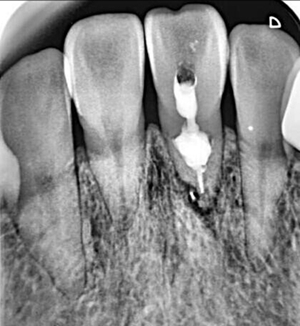

牙內吸收通常無明顯癥狀。根據(jù)吸收的類型和原因,主要分為炎癥性吸收和替代性吸收。其中,炎癥性吸收可能繼發(fā)于前期牙本質的細菌感染和創(chuàng)傷,牙本質吸收過程的進展不伴有吸收區(qū)鄰近部位硬組織的沉積,吸收部位可見大量肉芽組織,典型的影像學表現(xiàn)為,以根管為中心的橢圓形透光區(qū)。替代性吸收,導致根管內牙本質缺損的同時,在缺損區(qū)某些部位還伴有骨樣組織的沉積,造成牙髓腔不規(guī)則的擴大和根管連續(xù)性的破壞。根據(jù)牙內吸收發(fā)生部位和嚴重程度的不同,又可呈現(xiàn)不同的征象。若吸收部位發(fā)展至牙冠,可以觀察到牙冠上出現(xiàn)粉紅色的點,這是吸收細胞鄰近的結締組織高度血管化的結果。當吸收部位位于根方,則可使得根管原有的形態(tài)缺失,X線片可見根管局部氣球樣的膨大,通常邊界清晰。若牙髓還有部分的活力,則患牙可能有慢性牙髓炎的表現(xiàn);若牙髓完全壞死,則可能發(fā)展成根尖周炎,而出現(xiàn)相應的癥狀。竇道的出現(xiàn)往往是己發(fā)生慢性根尖膿腫或根管側穿的表現(xiàn)。由于患牙冠方的牙髓通常己經(jīng)壞死或被去除,因此敏感性測試常為陰性。

牙內吸收一旦確診,則需要對患牙的預后做出判斷。對于有保留價值的患牙,應該及時行根管治療。對于未發(fā)生根管側穿者,應完全去除根管內吸收組織,以防止其牙體硬組織的進一步破壞。牙內吸收所導致的病損的特點,給根管治療帶來了難度。行根管預備時,應盡量保守,以最大程度的保留牙體組織,以免對本就薄弱的根管壁造成進一步的損害。對于有活動性吸收的患牙,在治療過程中,炎癥牙髓和肉芽組織可能出現(xiàn)大量的滲血從而影響操作視野。同時,機械預備的方法往往不能完全達到吸收所造成的缺損部位。因此,根管預備時次氯酸鈉和超聲設備的作用就顯得尤為重要。次氯酸鈉可以溶解壞死的牙髓組織。超聲的震蕩可以使次氯酸鈉沖洗液活化,并充分滲透到根管系統(tǒng)的每個角落,以減少根管內細菌的數(shù)量。然而,即使使用了超聲設備,往往根管內局部還是會有細菌的殘留因此,根管內封藥應該具有良好的抗菌作用,以提高器械所不能到達部位的消毒。氫氧化鈣糊劑對根管內多種細菌有殺傷作用,并可滲入牙本質小管發(fā)揮殺菌作用,效果明顯。此外有研究證實,氫氧化鈣與次氯酸鈉有協(xié)同作用,可減少根管內有機碎屑的殘留囚。對于根管的充填,應選擇具有良好流動性的充填材料,來封閉吸收所造成的缺損。其中,熱塑性牙膠充填技術最為常用。

在一些病例中,牙內吸收己經(jīng)發(fā)展至牙根外表面,使得根管與牙周相連通,并可能出現(xiàn)鄰近牙周組織的病變。這就需要在根管治療的同時行穿孔的修補。礦物三氧化物凝聚體(mineral trioxide aggregate,MTA)具有良好的生物相容性和誘導成骨性,對根尖周組織的刺激小,并且和其他材料相比,其封閉性也更好,故常用來做穿孔的修補。當牙內吸收的缺損不可修復時,則只有選擇拔除。